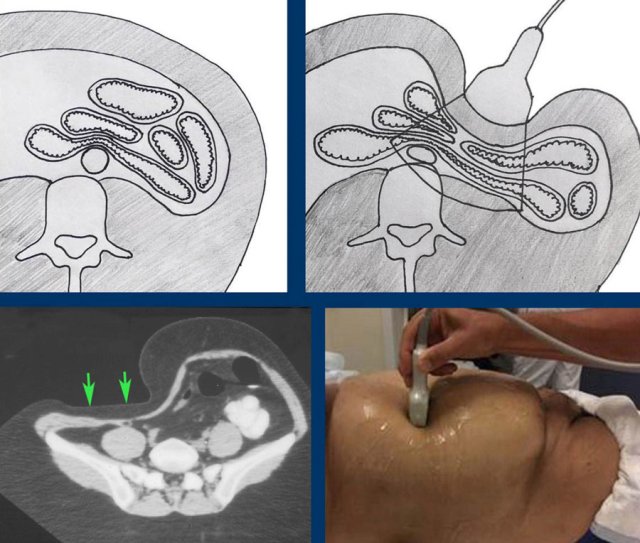

The CT scan shows how intra-abdominal anatomic relations are altered by graded compression.

During compression, the ventral wall of the bowel is compressed against the dorsal wall, eliminating the disturbing effect of gas and other bowel contents.

CT shows contracted colon (arrow) in obese patient.

During light compression (middle) the contracted colon can be visualized with a 12 MHz probe.

During moderate compression (right), the relaxed colon can even be seen flattened against the dorsally located psoas muscle.